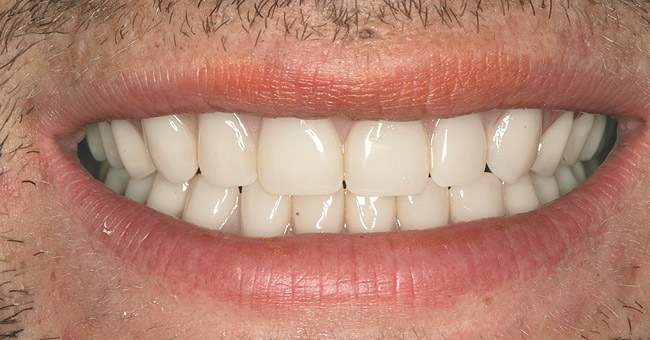

After his treatment was complete (Figure 7 and Figure 8), Joe wrote a letter to convey his gratitude. In part, it said:

I just wanted to say thank you for this opportunity that has really helped me in ways unimaginable. Now I can look in the mirror and see myself as I used to look before my addiction took hold of me. I now hold my head up proudly. I am no longer self-conscious about how I look and I have been clean for almost 2 years. With my new teeth, I now look clean as well. People look at me differently, and they treat me like I am a normal person! I feel whole. Thank you for my smile. You have changed my life!

Figure 7  FINAL RESULTS Completing dental treatment gave Joe a newfound sense of self-esteem.

Figure 7

Figure 8  FINAL RESULTS Completing dental treatment gave Joe a newfound sense of self-esteem.

Figure 8